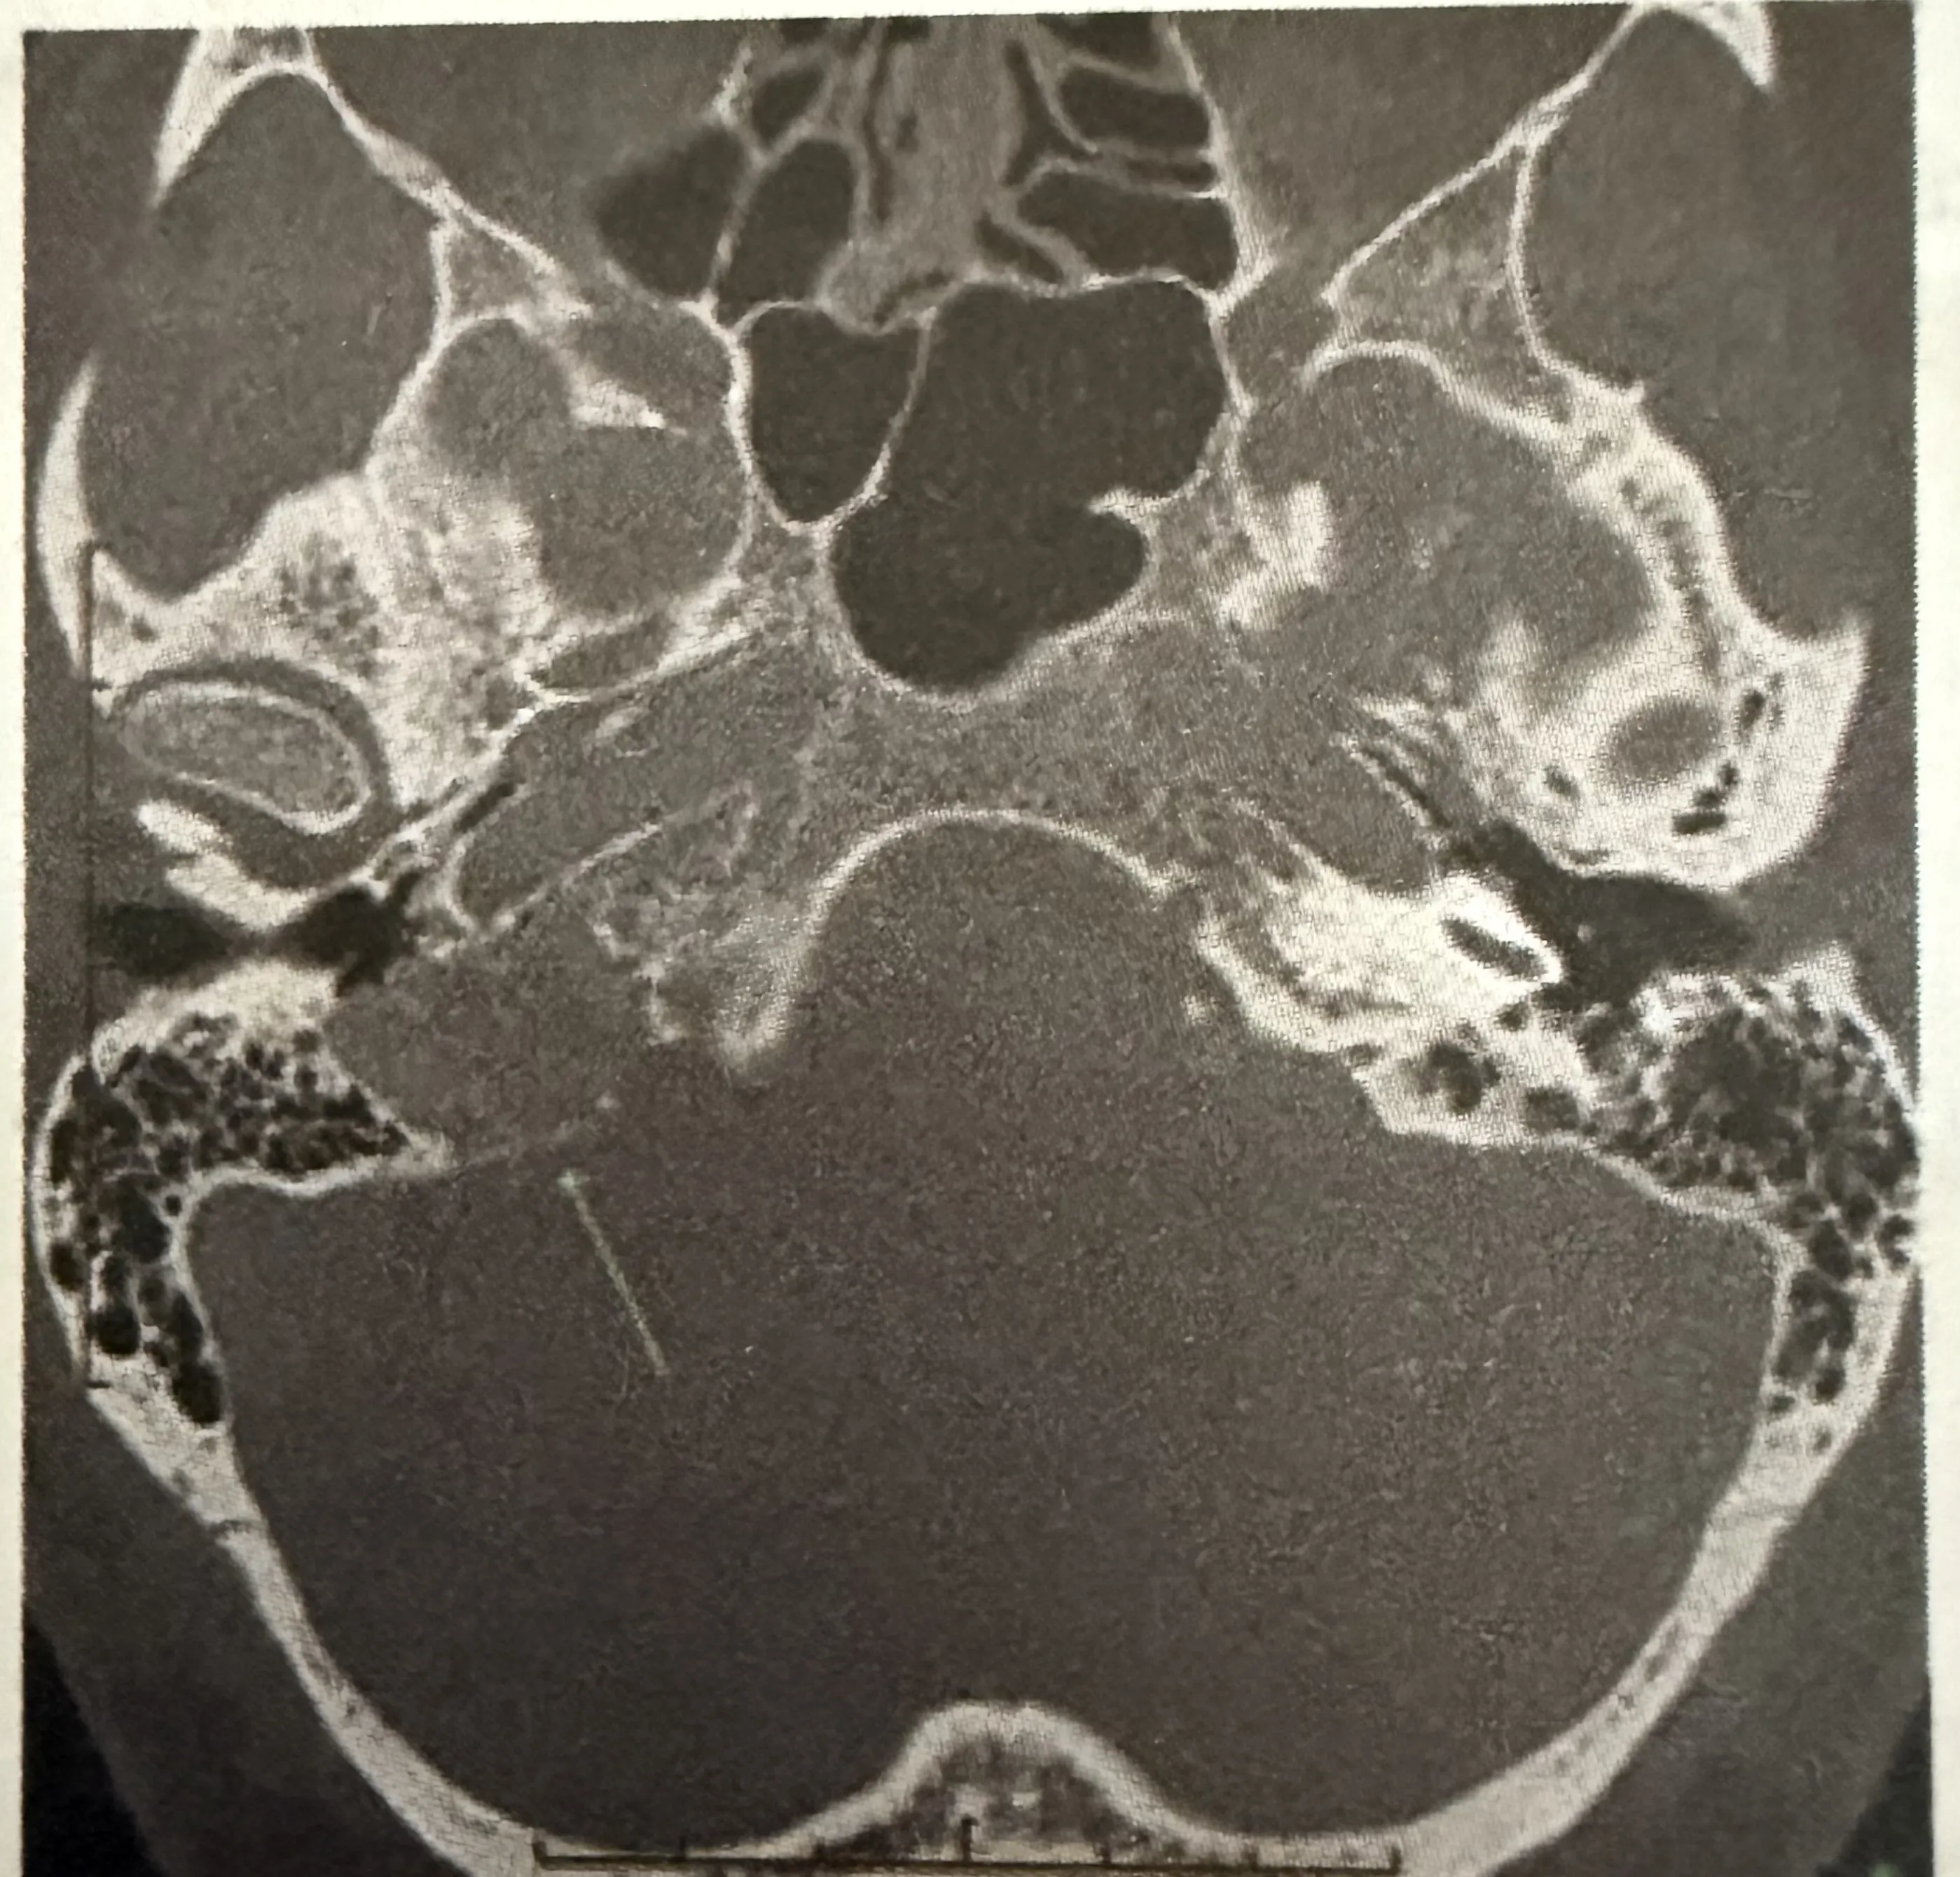

A patient presents with conductive hearing loss, pulsatile tinnitus, and a positive Phelps sign. Based on the CT scan image provided, what is the most likely diagnosis?

Explanation: ***Glomus Jugulare*** - The symptoms of **conductive hearing loss**, **pulsatile tinnitus**, and a **positive Phelps sign** (destruction of the bone separating the carotid artery from the jugular bulb on CT) are classic for a glomus jugulare tumor. - The CT scan image, showing a destructive lesion in the **jugular foramen** region, further supports this diagnosis, as these tumors originate from the paraganglia of the jugular bulb. *Glomus Tympanicum* - While it can cause conductive hearing loss and pulsatile tinnitus, a glomus tympanicum tumor is typically **confined to the middle ear cavity** and does not involve bone erosion of the jugular foramen as indicated by a positive Phelps sign. - The CT findings would show a mass in the middle ear, often behind an intact tympanic membrane, rather than extensive bone destruction in the jugular region. *Acoustic Neuroma* - This tumor, also known as a **vestibular schwannoma**, primarily causes **sensorineural hearing loss**, **tinnitus** (often non-pulsatile), and **balance issues**, not conductive hearing loss or pulsatile tinnitus. - An acoustic neuroma is located in the **cerebellopontine angle** and internal auditory canal, and the CT scan would show a mass in this specific location, not necessarily bone erosion of the jugular foramen. *Cholesteatoma* - A cholesteatoma is a **destructive, expanding growth of keratinizing squamous epithelium** in the middle ear or mastoid, typically presenting with **conductive hearing loss**, **otorrhea**, and sometimes headaches. - It does not typically cause pulsatile tinnitus unless it's very large and vascularized, nor does it present with the characteristic destruction of the jugular foramen seen with a positive Phelps sign.

A patient presents with conductive hearing loss, pulsatile tinnitus and a positive Phelps sign. Using the CT scan provided, identify the condition.

Explanation: ***Glomus jugulare*** - This diagnosis aligns with the presence of **conductive hearing loss**, **pulsatile tinnitus**, and a **positive Phelps sign**, which indicate a highly vascular tumor in the jugular foramen. - While exact details of the CT scan are difficult to discern from the provided image, the clinical context strongly points towards a **glomus jugulare tumor**, known for its characteristic bone erosion around the jugular bulb seen on imaging. *Glomus tympanicum* - This typically presents with **pulsatile tinnitus** and **conductive hearing loss**, but is usually observed as a red mass behind an intact tympanic membrane, arising from the **promontory** within the middle ear space. - It would not typically cause a **Phelps sign**, which specifically relates to erosion of the jugular foramen region. *Acoustic neuroma* - An acoustic neuroma (vestibular schwannoma) causes **sensorineural hearing loss**, often unilateral, not conductive, along with **tinnitus** (usually non-pulsatile) and **balance issues**. - It arises from the vestibular nerve within the **internal auditory canal** and cerebellopontine angle, and does not cause a Phelps sign. *Otosclerosis* - Otosclerosis is characterized by **conductive hearing loss** due to abnormal bone growth fixing the stapes in the oval window, but it does not cause **pulsatile tinnitus** or involve a **positive Phelps sign**. - The disease involves the **otic capsule** and typically does not present with a tumorous mass visible on CT in the jugular foramen area.